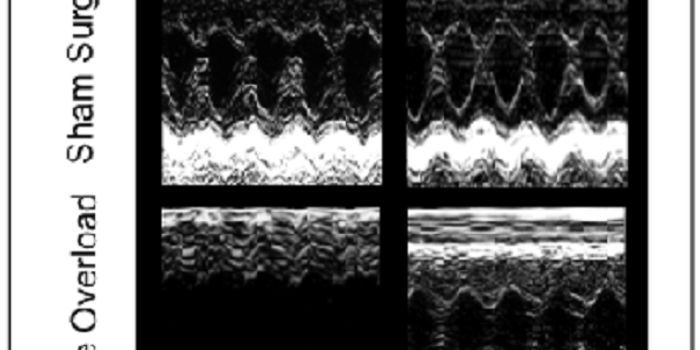

JUL 07, 2016CardiologyWhether you let it all out or bottle it up, arguments between spouses align with specific health problems, report resear ...